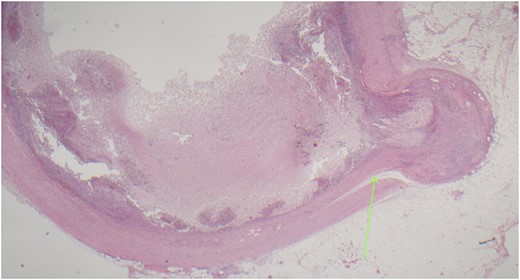

On examination, the patient was alert, but was grimacing in pain. Her abdomen was soft but extremely tender on the right iliac fossa (RIF) region with positive Rovsing’s sign, and rebound tenderness was noted. Vitals were stable. The white cell count was 16.8 × 109/L with left neutrophil shift. The CRP was 102 mg/L. Other laboratory investigations were unremarkable. A computed tomography (CT) scan of the abdomen showed a thickened appendix with adjacent fat stranding which was consistent with acute appendicitis (Figs 1 and 2). Intravenous Augmentin was given pre-operatively and laparoscopic appendectomy was performed on the same day. The patient recovered uneventfully and was discharged the next day. The histological reports revealed appendiceal diverticulitis with transmural mixed inflammation extending out into subserosa and serosa (Fig. 3).

Acutely inflamed appendiceal diverticulum with transmural mixed inflammation extending out into subserosa and serosa.